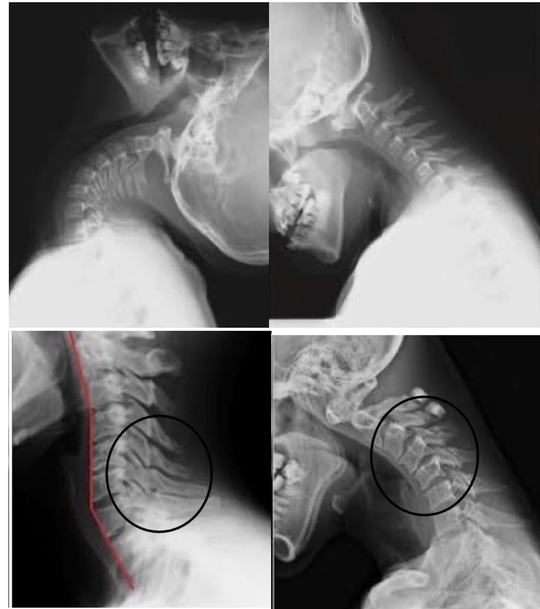

首の中でも動きやすい場所、動きにくい場所にわかれる

〇は過剰に動いてしまう

■はコリ感や張り感を感じるだけでなく、構造的に動きを失いやすい場所になります。

そのため、頸椎の中でも上部は可動性が失われやすい場所になっているし、胸椎も可動性が失われやすい場所になります。

よって、動きやすい部位と固まる部位に分かれるように構造的になります。

上位頸椎と上位胸椎が固まりやすくなりやすい場所になり、過剰に動いてしまう下位頸椎にヘルニアが多くなります。

シワの部分は過剰に動くことを表している